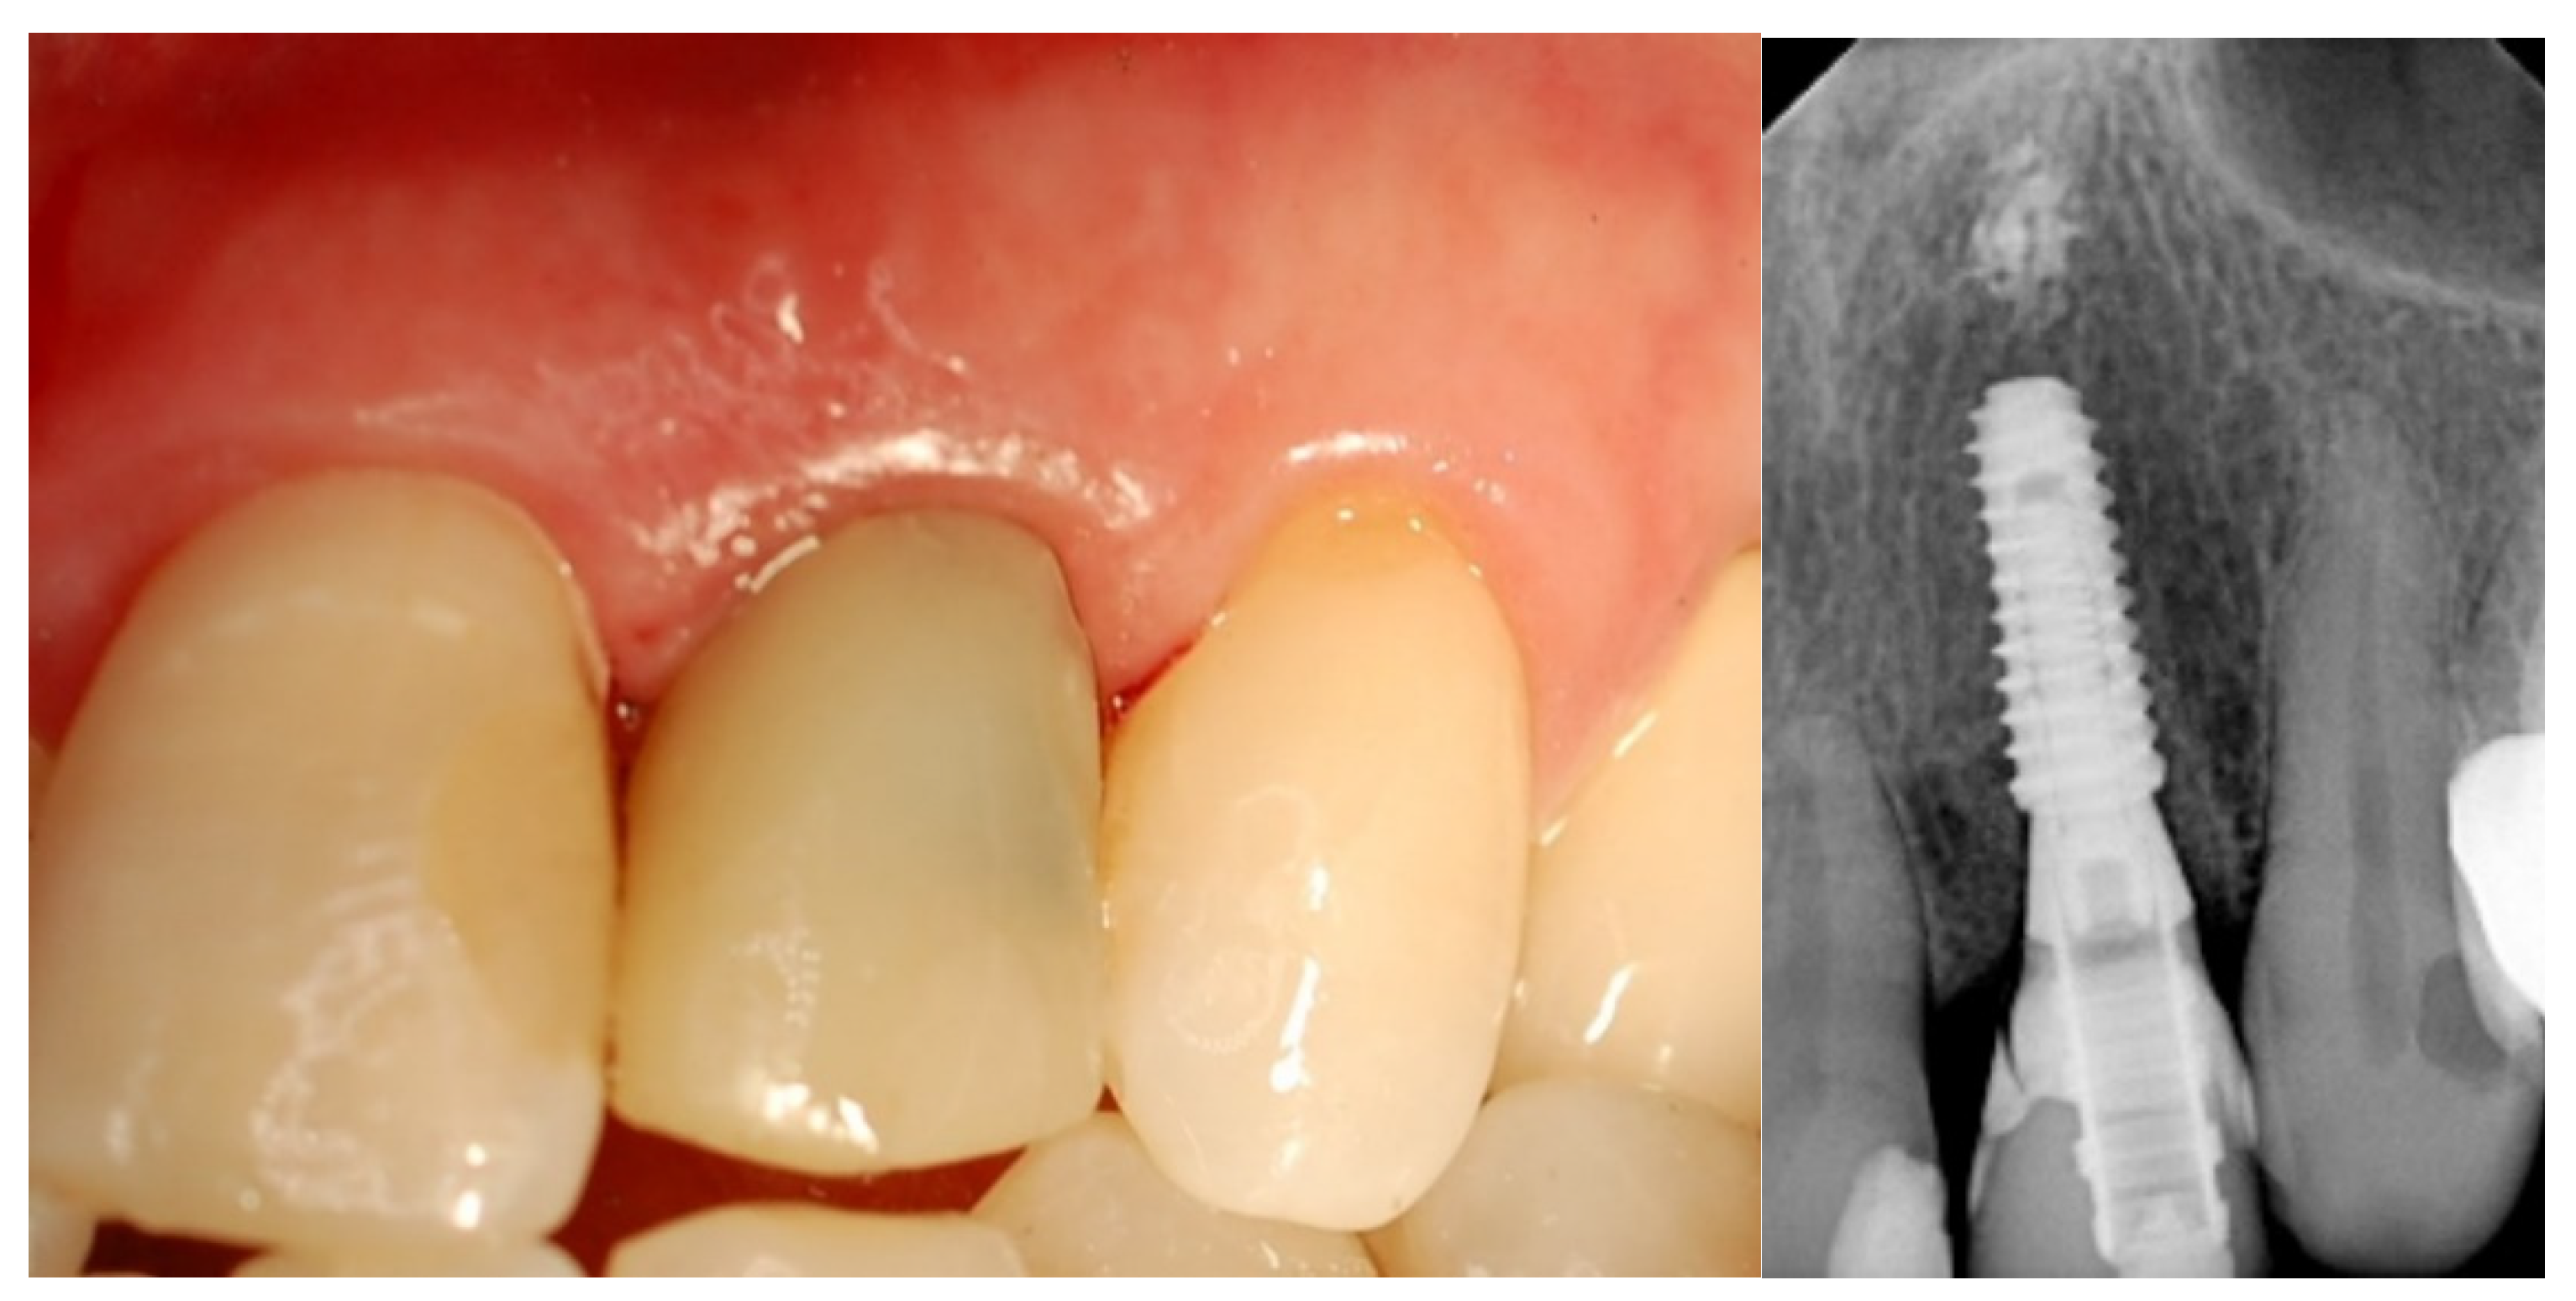

- Esthetic evaluation of clinical pictures, including at least two adjacent teeth, taken at two years after loading was done following the pink esthetic score (PES) proposed by Fürhauser et al., in 2005 [31]. In brief, the PES score evaluates seven variables: mesial papilla, distal papilla, soft tissue level, soft tissue contour, alveolar process deficiencies, soft tissue color and texture. A 0-1-2 scoring system was used, with a maximum achievable score of 14 per site.

| PES 3 at the 2-year follow-up | 12.6 ± 0.97 | 12.2 ± 0.92 | 0.3554 |